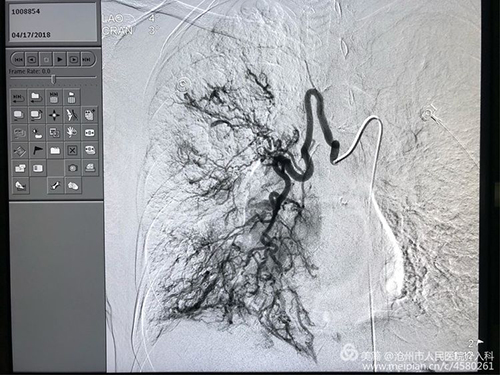

患者女性,67岁,大咯血,重度支气管扩张并感染、肺结核、肺气肿病史30余年,并肺动脉高压、肺心病、右心衰。曾于县、市多家医院及北京协和医院多次治疗心肺功能极差,外院应用止血药物无效,转入我科。下图为术前CT急诊行介入治疗,术中造影可见双侧支气管动脉均异常粗大,是出血的罪犯血管。栓塞后患者咯血即停止,效果立竿见影。

右侧病变支气管动脉